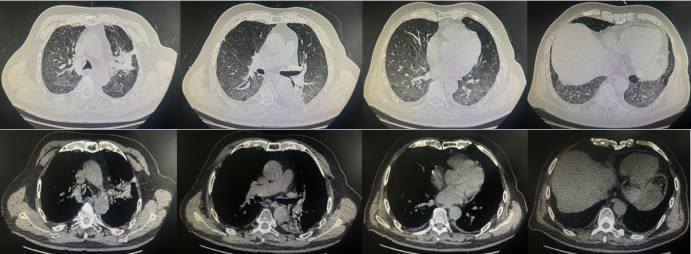

辅助检查:血常规示WBC 2.12×109/LNEU 1.4×109/LLYM 0.4×109/L,均显著降低;Hb 100 g/L,轻度贫血;SAA 23.75 mg/LCRP 21.5 mg/L,炎症指标轻度升高;IL-63.47 pg/mlPCT 0.12 ng/ml;痰培养检出鲍曼不动杆菌。胸部CT示左肺斑片状高密度影双肺间质改变伴炎症渗出,左侧少量胸水(图2)

图片

2  患者第一次住院期间胸部CT(2025-08-19)